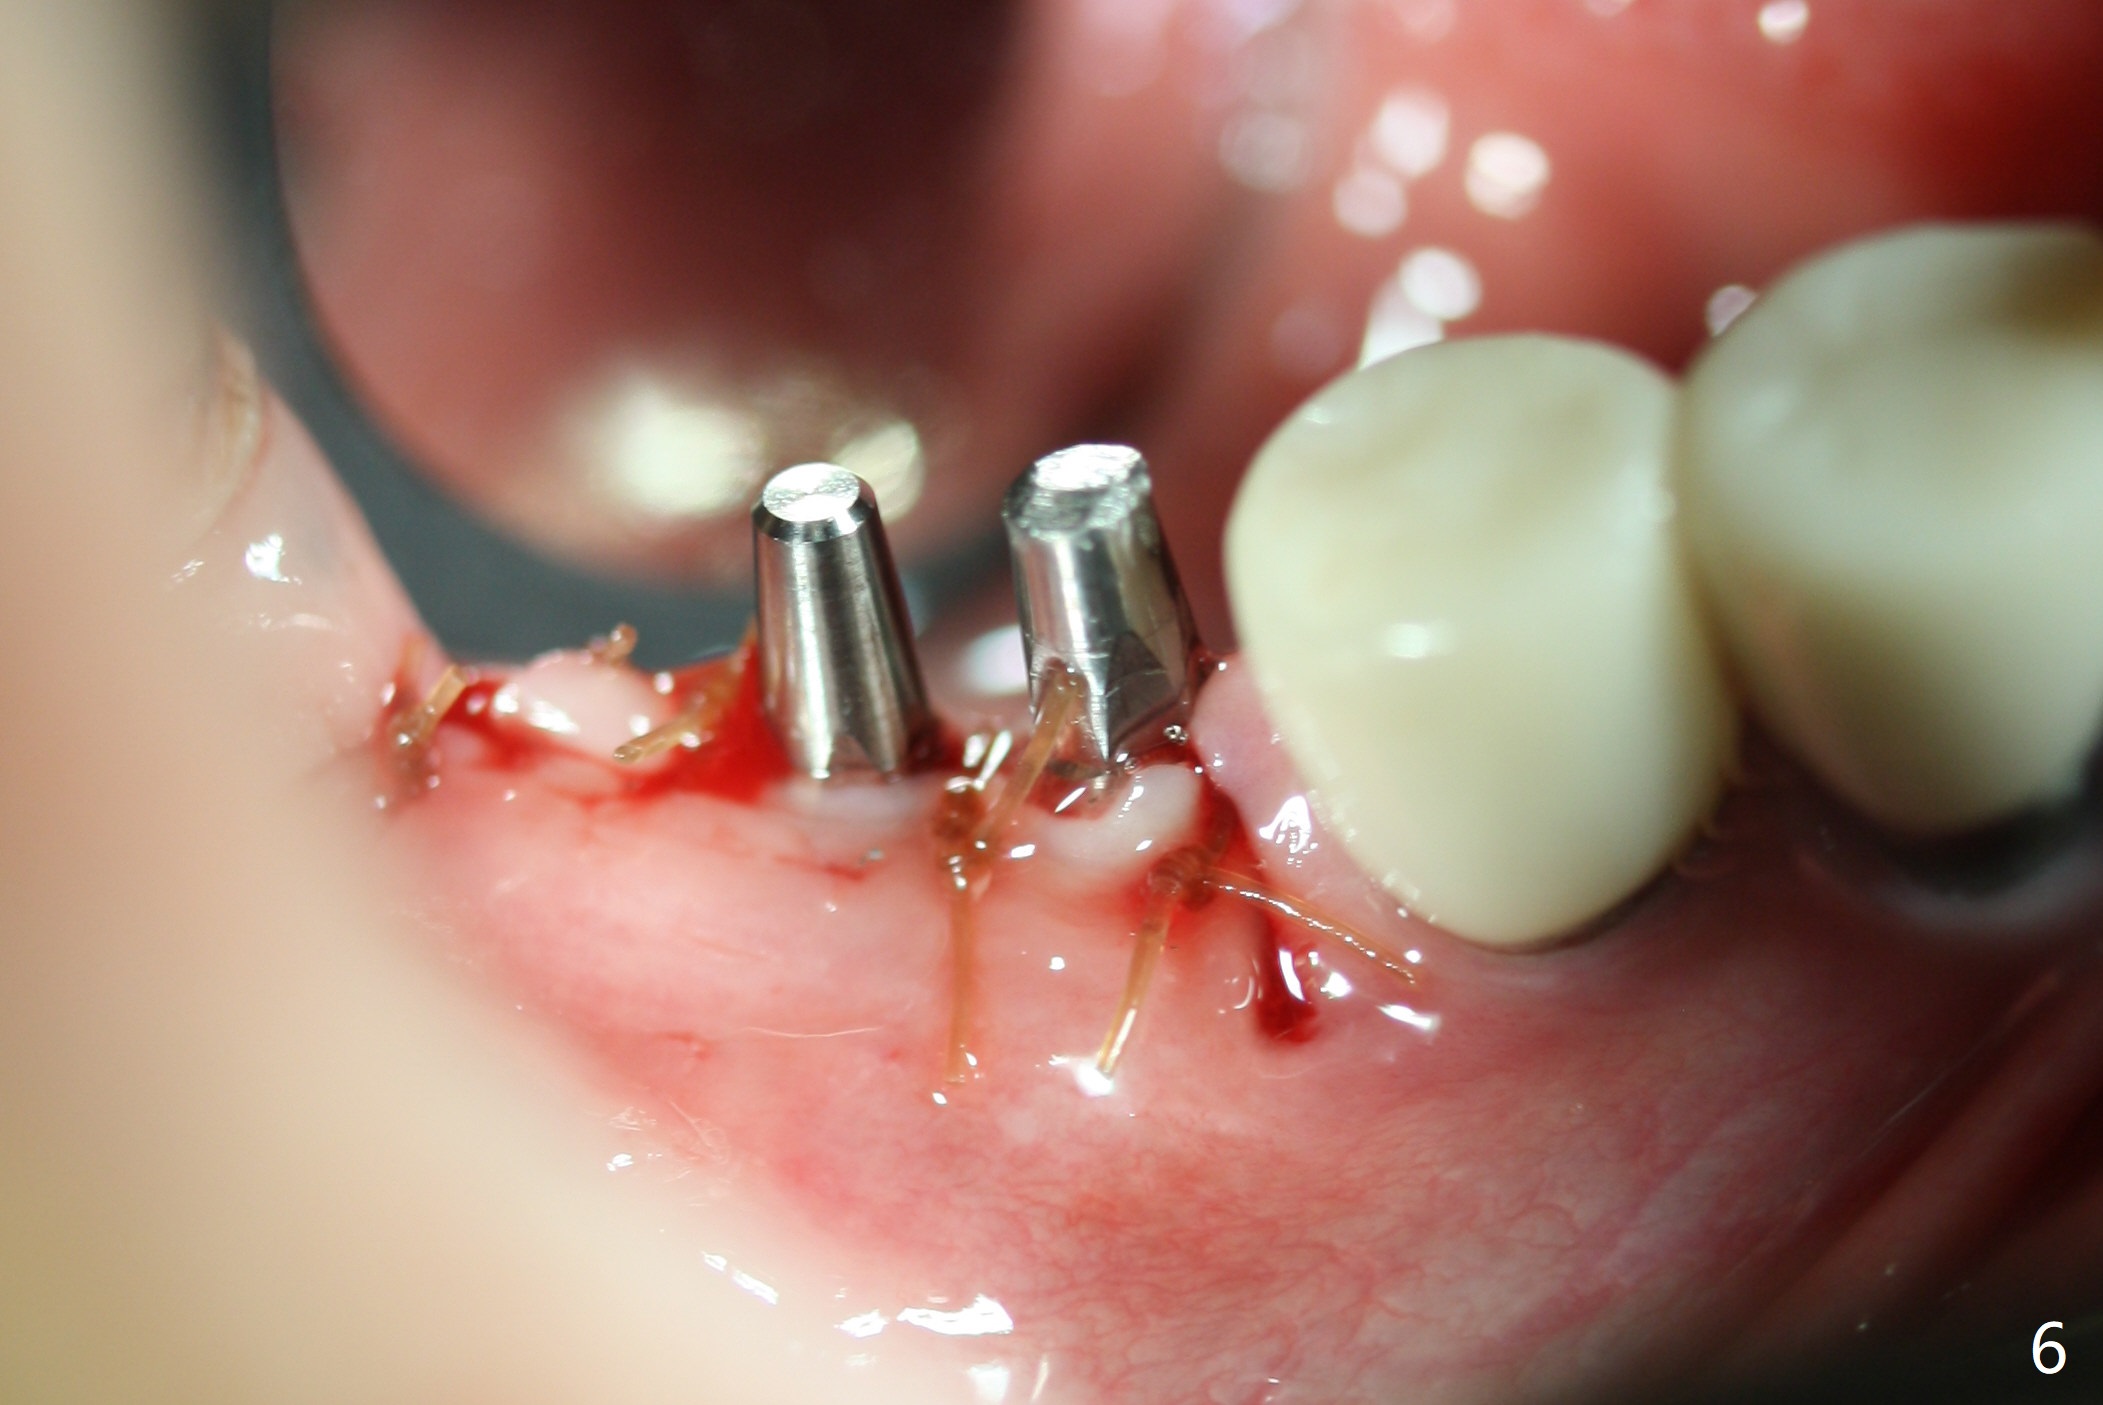

Two of 2.5 mm 1-Piece Implants M

The edentulous ridge at #30 is narrow (Fig.1). After ridge reduction, osteotomy is initiated with 1.2 mm drill for 10 mm; the mesial osteotomy is to be changed (Fig.2 red line). Using a 1.2 mm drill placed in the distal osteotomy (Fig.3 D), the mesial osteotomy changes in trajectory with subsequent placement of a 2.5x10(4) mm 1-piece implant. Since the mesial implant is high in occlusion, the cuff of the distal implant is changed to be 2 mm (Fig.4 (shorter black line)). Panoramic X-ray is taken to show no violation of the Inferior Alveolar Canal (Fig.5 red dashed line). These two 1-piece implants are slightly lingually placed (Fig.6). The crestal bone around the implants resorbs without thread exposure 5 months postop (Fig.7). Impression is taken for a splinted crown (Fig.8-12). There is no metal show around the 2.5 mm 1-piece implants 6 months postop (advantage) vs. that at #28 and 29 (Fig.13). Bitewing is taken post cementation to determine whether residual cement is present (Fig.14). There is periodic swelling and pain in the lower right quadrant 2 years post cementation (Fig.15). In fact periimplantitis appears to have developed at #28 (Fig.16) with loss of the buccal bone (Fig.17,18). The buccal bone loss is less at #29 (Fig.19) and #20 (Fig.23) and no at #30 mesial and distal implants (Fig.20,21). A much smaller implant will be placed lingually at #28 immediate (Fig.24,25).